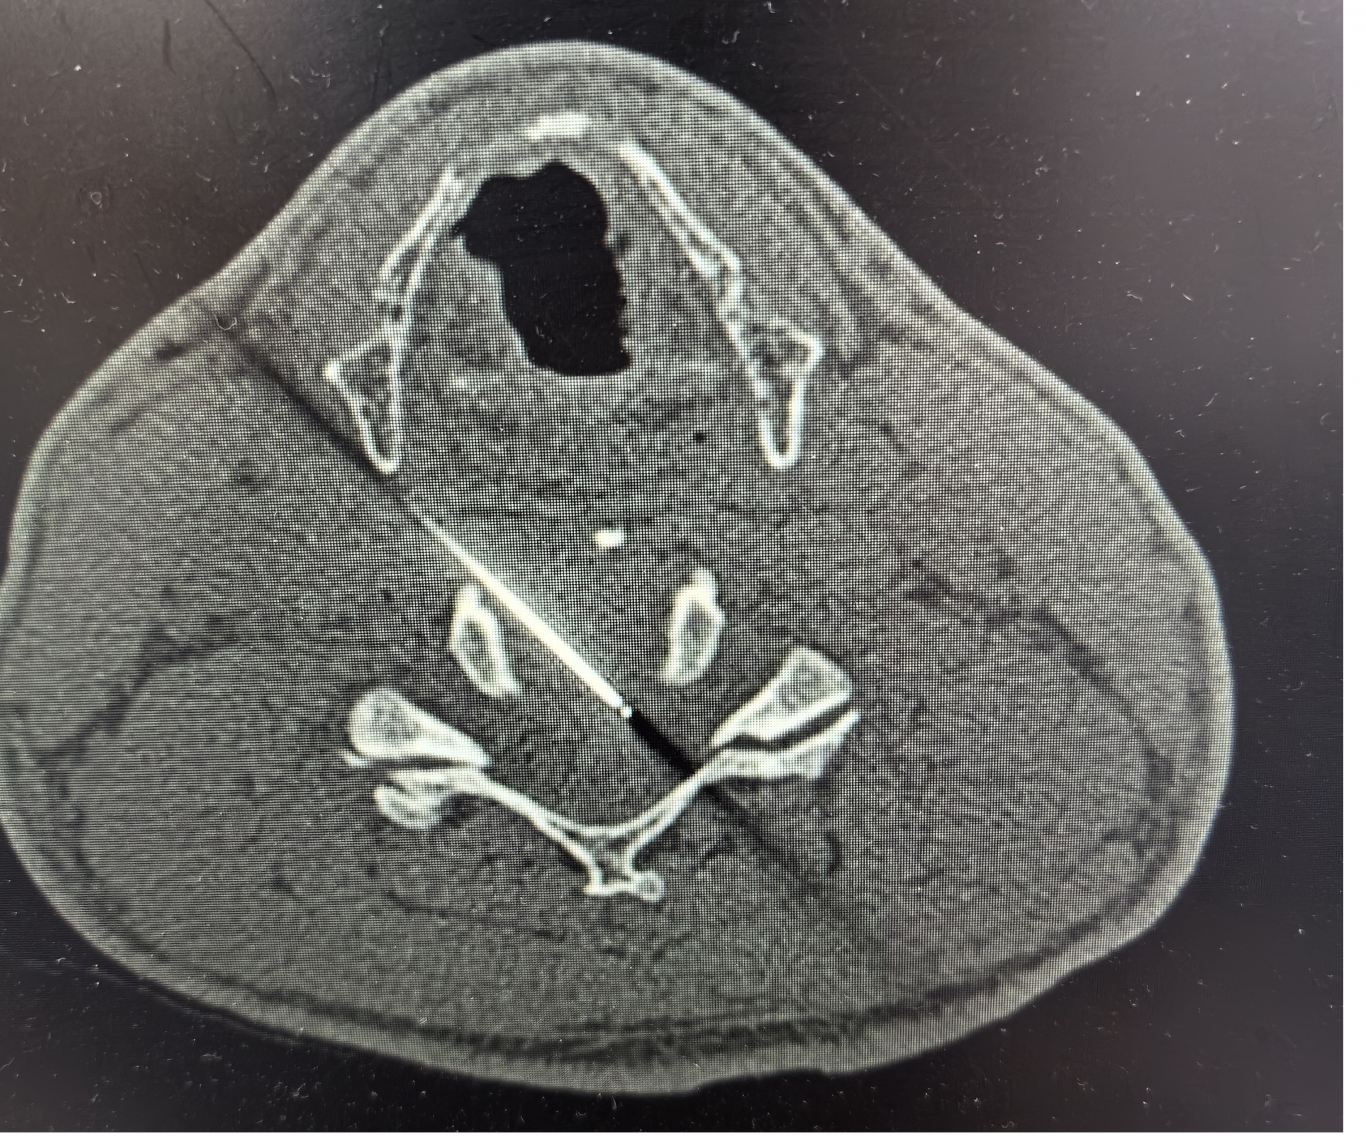

手術(shù)之后3天,黃大伯疼痛得到很好緩解,露出了許久沒有的笑容,終于可以安心躺著睡覺了,1個月后基本恢復(fù)了正常生活,6個月后復(fù)查CT發(fā)現(xiàn)突出的頸椎間盤已經(jīng)基本消失了,黃大伯一家人對治療效果非常滿意。

手術(shù)之前CT,巨大突出物 術(shù)后6個月復(fù)查CT:突出物消失